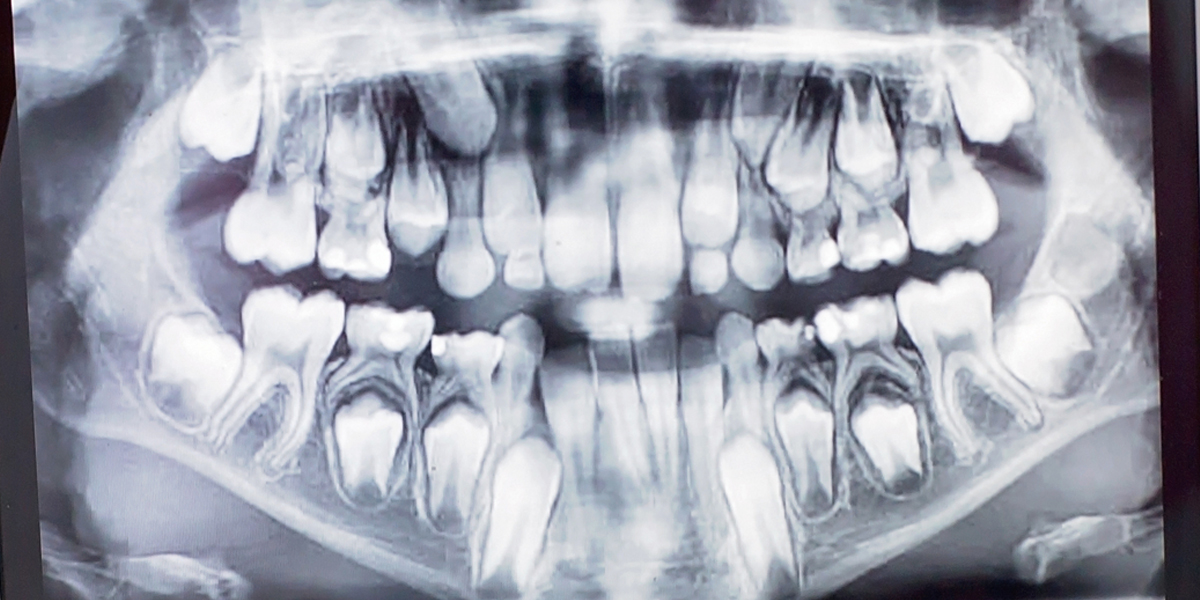

EF indeks izračuna ortodont na pregledu, ko pri otroku vzame odtis zgornjih in spodnjih zob. Na odtisih in z odčitavanjem ortopana naredi analizo stanja, ki je obvezna ortodontska storitev. S tem dobi število točk, ki jih dokumentira v zdravstveni karton pacienta.

Primer fotografij, ki jih potrebujemo za izračun EF indeksa:

Preden izpolnite obrazec za brezplačen prvi pregled za EF index, posnamite zobovje vašega otroka, tako kot prikazujejo zgornje fotografije in jih priložite k obrazcu. Lahko pa nam preprosto zahtevo po prvem on-line pregledu vključno s fotografijami pošljete na naslov info@ortodont-takoj.si